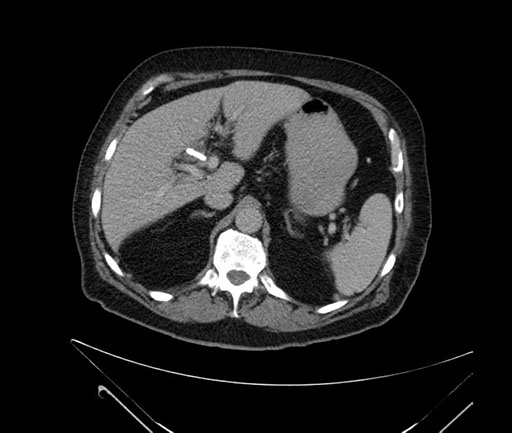

Imaging Analysis

Look through the patient's CT scan to identify any areas of concern for the necessary procedure.

Based on your CT findings, which issue(s) would give reason for "planned slowing down moment(s)" in this case?